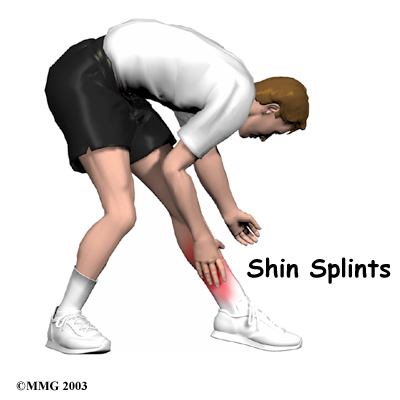

Shin Splints

Pain along the front or inside edge of the shinbone (tibia) is commonly referred to as shin splints. The problem is common in athletes who run and jump. It is usually caused by doing too much, too quickly. The runner with this condition typically reports a recent change in training, such as increasing the usual pace, adding distance, or changing running surfaces. People who haven't run for awhile are especially prone to shin splints after they first get started, especially when they run do...